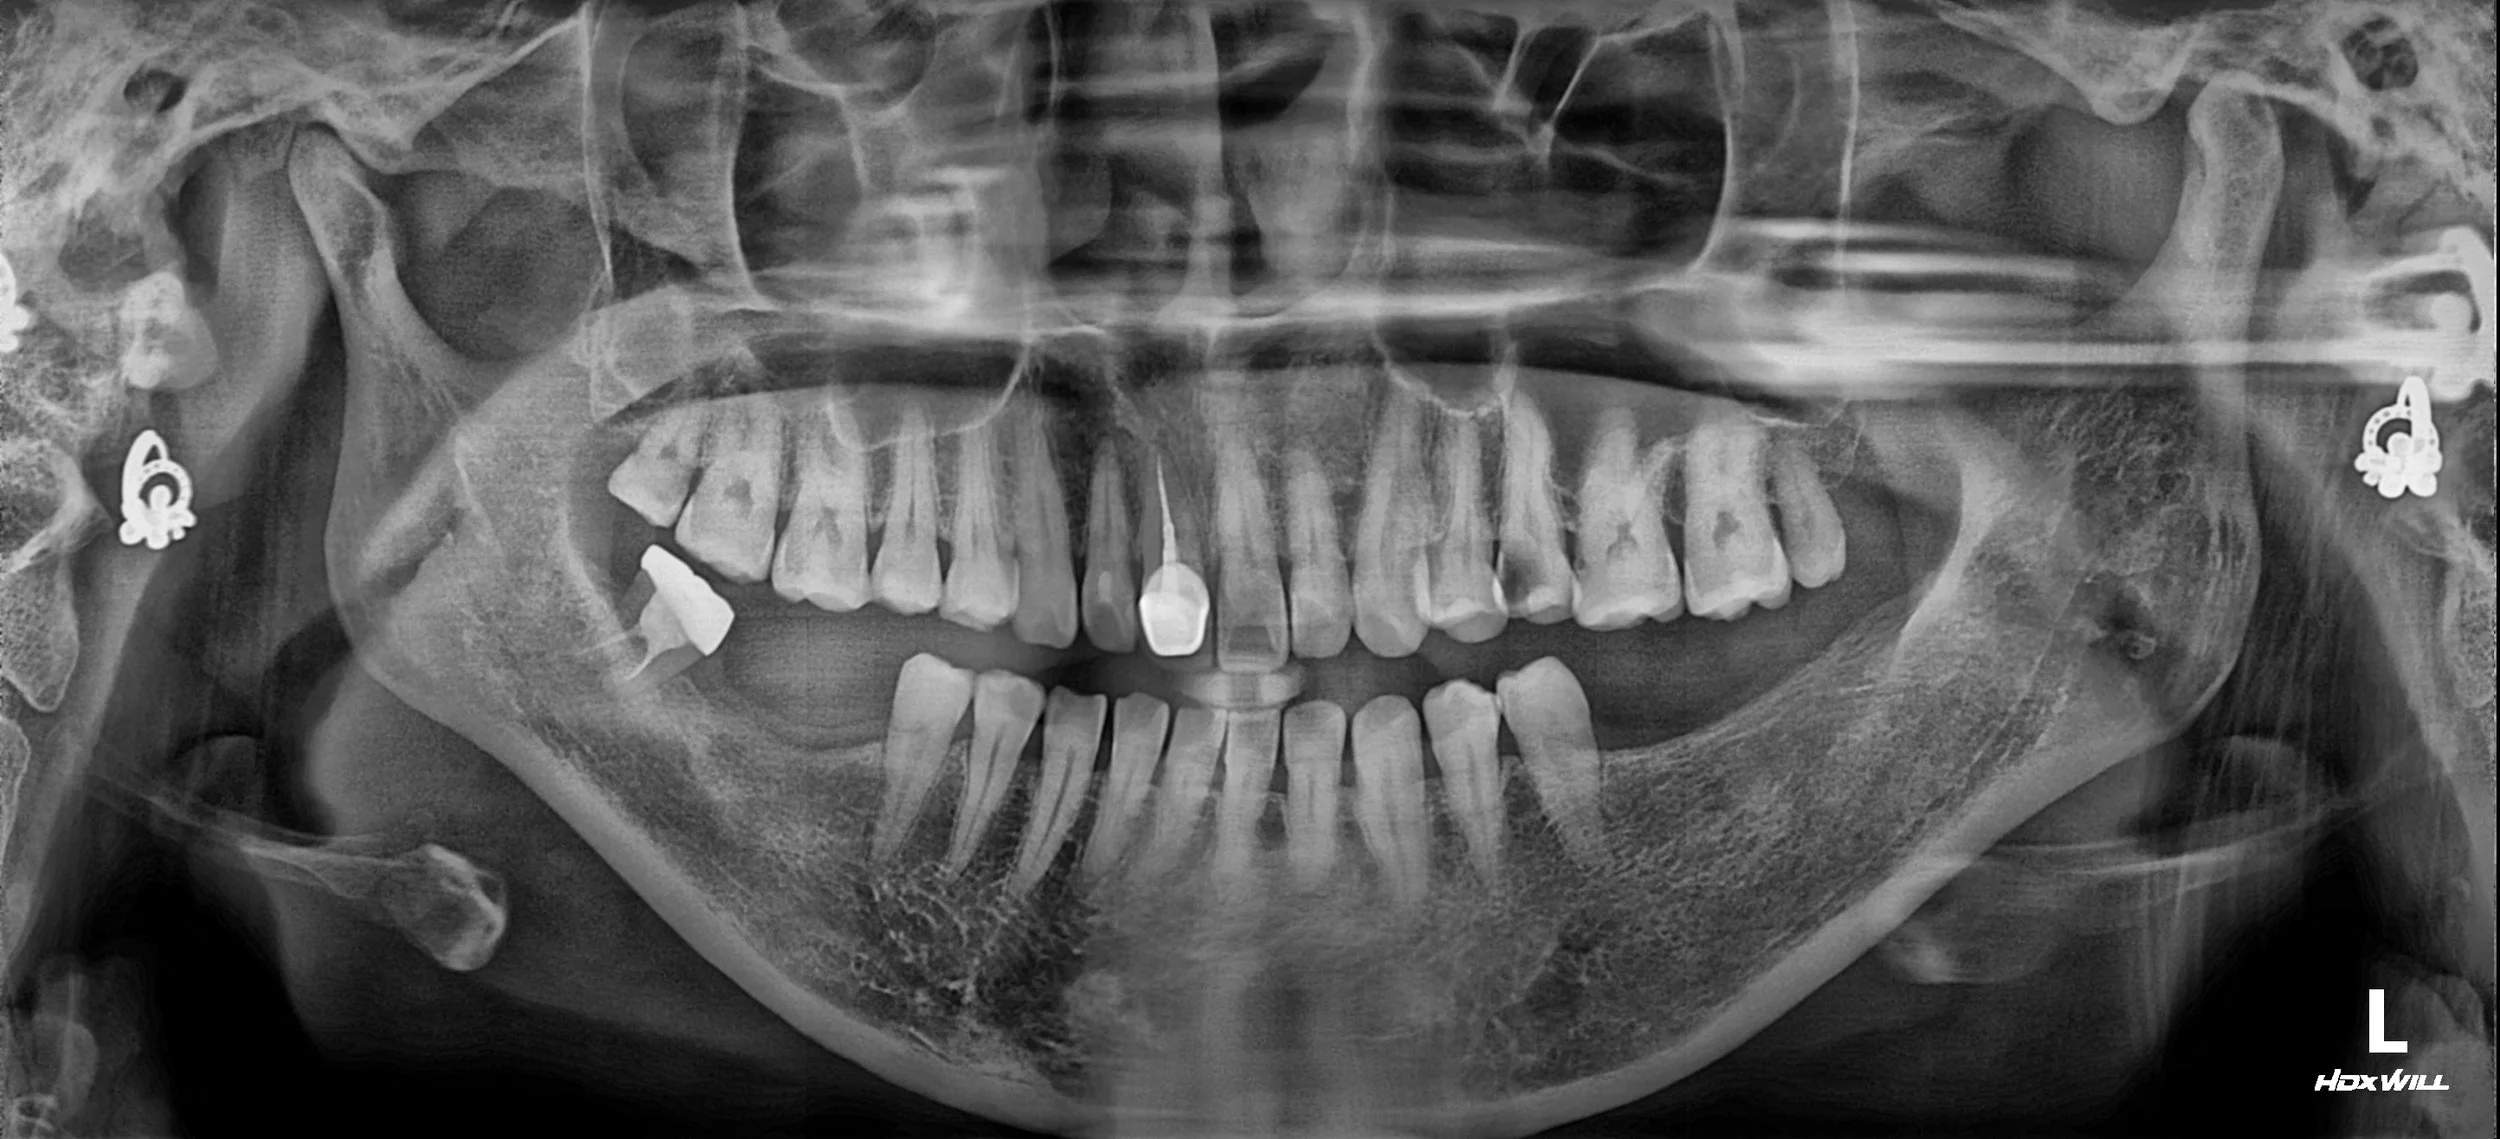

A female patient in her 30s presented with chronic TMJ discomfort and a noticeable shifting of the jaw upon closure. Clinical and radiographic evaluation revealed a complex occlusal disharmony:

• Posterior Bite Collapse & Supra-eruption: The long-term loss of mandibular posterior teeth had allowed the opposing maxillary molars to erupt downward (supra-eruption), disrupting the occlusal plane.

• Pathological Mandibular Deviation: A premature contact at tooth #48 acted as a functional interference, forcing the mandible to deviate from its natural path during closure.

• TMJ Dysfunction: This constant displacement had led to chronic muscle tension and symptomatic TMJ distress, significantly impacting the patient's quality of life.

OPG - BEFORE